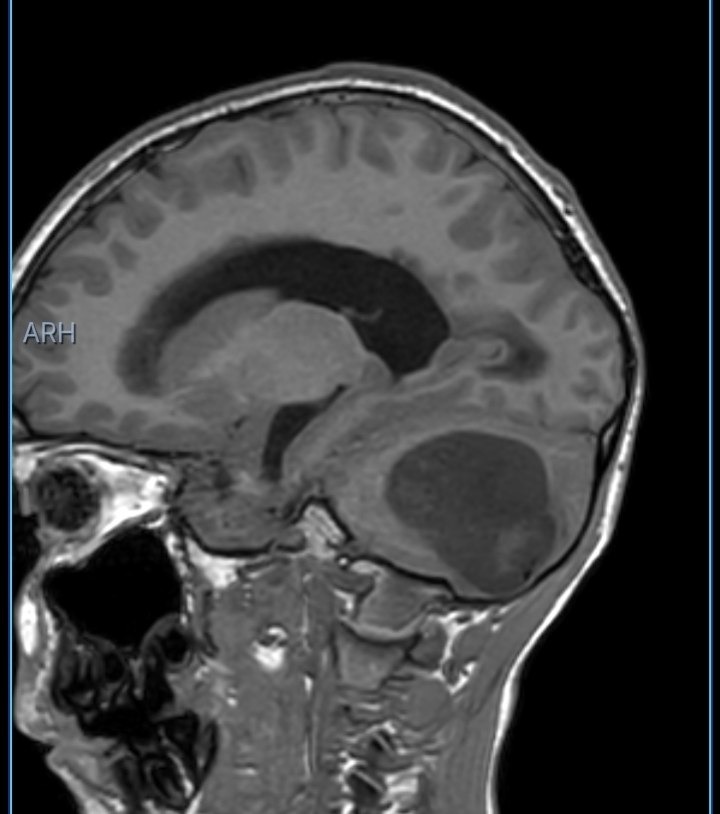

Sebasthian González is a 10-year-old boy from Isla Margarita, Venezuela, who has recently been diagnosed with a large arachnoid cyst located in the posterior part of his brain.

Over the past weeks, Sebasthian began suffering from severe headaches, persistent morning vomiting, and worsening neurological symptoms. After urgent medical evaluation, doctors confirmed that the cyst is causing obstructive hydrocephalus and severe intracranial hypertension, a condition that cannot be left untreated.

According to the medical report, Sebasthian requires immediate hospitalization and the placement of a ventriculoperitoneal shunt to relieve the dangerous pressure in his brain, followed by a second surgical procedure to treat and remove the lesion. Without timely intervention, the risk of serious neurological damage — and even life-threatening complications — is real.